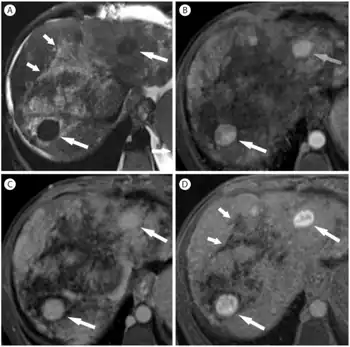

| Budd–Chiari syndrome secondary to cancer, note clot in the inferior vena cava and the metastasis in the liver | |